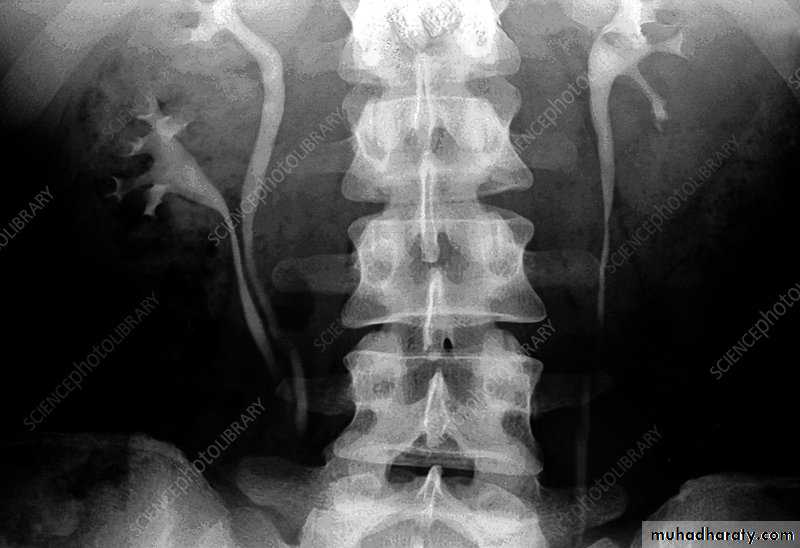

Radiological DiagnosisAbdominal U/S show various degree of hydronephrosis and ureter not dilated and evaluate parenchymal thickness

IVU same finding of U/S in addition evaluate function of the kidney